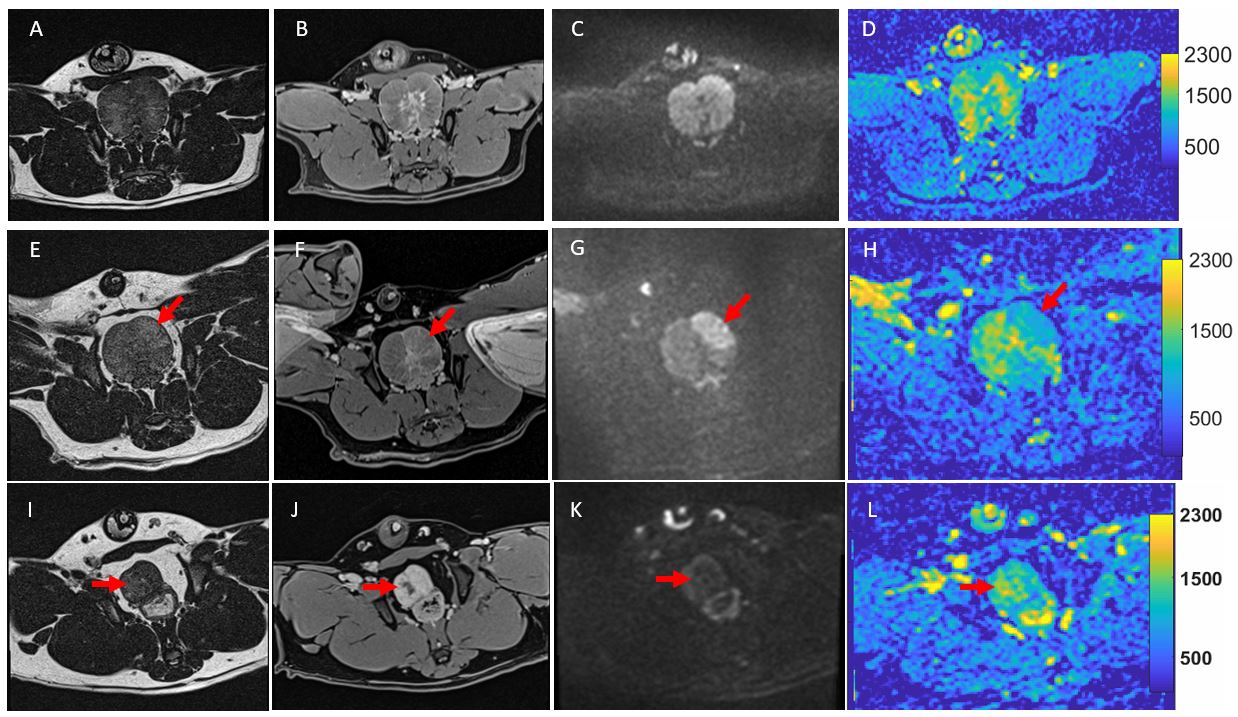

T2-weighted, post-contrast T1-weighted, diffusion-weighted images and ADC maps for pre-90Y (top panel), 3-day post-90Y (middle panel) and 40-day post 90Y (bottom panel). T2-weighted images are shown in first column (A, E, I); post-contrast T1-weighted in 2nd column (B, F J); diffusion-weighted in 3rd column (C, G, K); and ADC maps in 4th column (D, H, L). Arrows point to the treated lobes of the prostates.